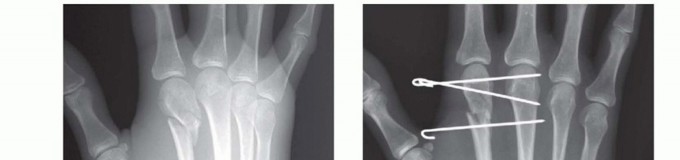

TECH FIG 4 • A-C. Patient with torsional injury to long and ring fingers leading to spiral fractures of the third and fourth metacarpals. The combined injury made it possible for malrotation to develop. D.

TECH FIG 4 • (continued) G,H. Motion at 6 weeks after surgery. The periosteum is elevated at the fracture site to assist with assessment of fracture reduction. As much of the interosseous muscle is left attached to the metacarpal as feasible to preserve blood supply to the bone.The fracture is reduced and provisionally stabilized with reduction clamps (TECH FIG 4D).

LAG SCREW FIXATION

Long oblique and spiral fractures whose lengths are at least twice the diameter of the bone at the level of the fracture are amenable to limited fixation with screws only (see TECH FIG 4A-C).Appropriately sized lag screws (1.4 to 2.7 mm) are placed. Typically, two or three screws are used (TECH FIG 4E,F).The first screw is placed perpendicular to the fracture in order to compress it and the second screw is placed perpendicular to the bone to resist longitudinal forces.In order to get proper compression with a lag screw construct, it is important to overdrill the near cortex.When using a 2.0-mm screw system, a 1.5-mm drill bit is used to drill both cortices. The near cortex is then overdrilled with a 2-mm drill bit.A countersink is used to maximize contact between the head of the screw and the bone. The size of the screw is measured and an appropriately sized screw is placed.The periosteum and interosseous muscle fascia are reapproximated to cover the screws. The juncturae tendinum are repaired and the skin is closed in standard fashion.The hand is then immobilized with the MP joints flexed 70 to 90 degrees with a forearm-based splint. Early motion can be started as early as 4 to 7 days, depending on fracture stability (TECH FIG 4G,H).